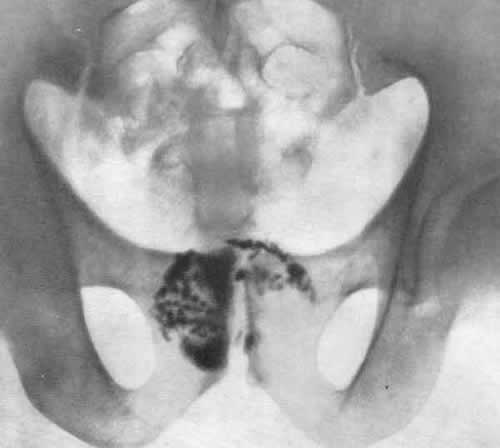

Основным методом диагностики простатолитиаза следует считать УЗИ, причем желательно с фиксацией картины на снимке. Наличие снимка позволяет не только подтвердить факт наличия простатолитиаза, но и достаточно точно отметить количество, локализацию, величину и плотность имеющихся конкрементов.

• Осуществить постепенное разрыхление камня, находящегося в открытой полости, применяя для этого инсталляционные литолитические композиции. Разрыхление наблюдалось у всех пациентов и зафиксировано на снимках.

Проведенная массажно-литолитическая терапия у 50 больных с осложняющими простатит камнями показала следующие результаты. Во всех случаях, контрольная УЗИ-грамма показала выраженное снижение плотности, числа и размеров теней имевшихся конкрементов. У всех пациентов снизилась интенсивность болевых симптомов, имевшихся в начале массажно-литолитического цикла. Каких-либо осложнений или повышения болевой симптоматики ни у кого из больных в процессе лечения не наблюдалось. Более того, снижение болезненности массажного простатолитолиза наступило во всех случаях.